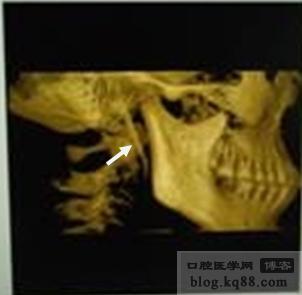

圖6右側(cè)莖突三維影像

圖6

2 CBCT采用錐形束X射線,在單次掃描獲得完整圖像。從而獲得頜面部三維數(shù)字圖像信息。CBCT數(shù)據(jù)可在初次重建獲得的軸位圖像上進(jìn)行多向、多平面重建(MPR)及曲面斷層或三維重建。除去莖突周圍組織影像干擾,只保留莖突影像,立體顯示莖突長度、粗細(xì)和方向,既能顯示莖突本身,又能顯示莖突舌骨韌帶的鈣化。利用多平面、多角度旋轉(zhuǎn)技術(shù)可清晰觀察莖突過長的立體解剖及其與周圍組織的關(guān)系,有利于臨床手術(shù)方案的制定和手術(shù)徑路的選擇。

總之,CBCT重建能清楚、直觀地顯示莖突在三維空間的全貌,準(zhǔn)確地測量其長度、角度以及反應(yīng)其與周圍組織結(jié)構(gòu)的關(guān)系。是目前診斷莖突過長綜合征的一種準(zhǔn)確、理想的檢查方法。